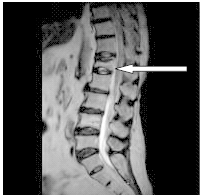

Na obrazie rezonansu magnetycznego strzałką wskazano patologiczny kręg

A. L₁

B. L₃

C. Th₈

D. Th₁₀